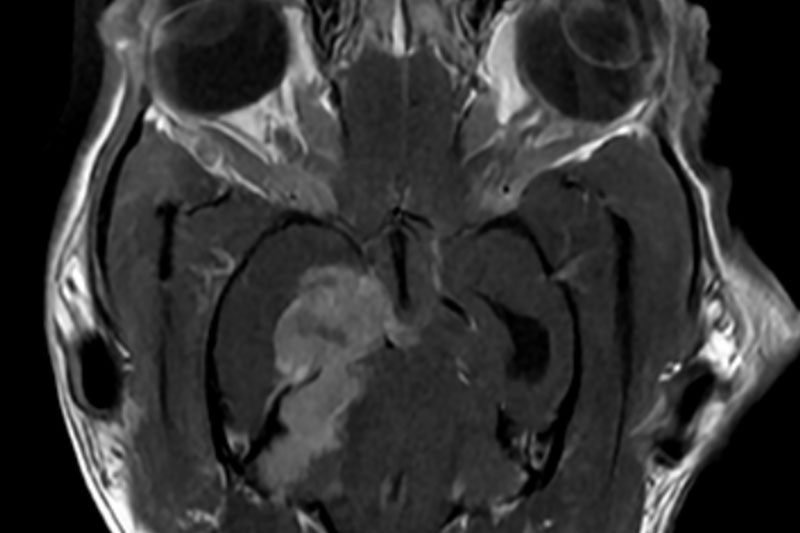

본 병원은 GE사의 1.5T 고해상도 자기공명영상장치(MRI)를 이용하여, 자기장을 이용한 비침습적 방식으로 뇌, 척수, 근골격계 등 다양한 연부조직을 정밀하게 영상화할 수 있습니다. MRI는 방사선을 사용하지 않아 반복 촬영에도 안전하며, 신경계 및 연부조직에 대한 탁월한 해상도를 제공하여 정확한 진단에 매우 유용합니다.

또한 본원의 MRI 장비는 GE사의 PROPELLER 기법을 도입하여 호흡이나 움직임에 따른 영상 왜곡을 최소화하면서도 검사 시간을 단축시켜, AI 기반 영상 처리 기술을 통해 노이즈를 줄이고 더욱 선명하고 명확한 영상을 획득할 수 있습니다. 이러한 기술적 강점을 바탕으로 마취 시간과 그에 따른 환자의 부담을 줄이면서도, 진단에 충분한 고화질 영상을 안정적으로 확보할 수 있습니다.

| 뇌/두개강 | 뇌종양, 뇌염, 수두증, 간질, 뇌출혈, 시신경 이상 등 |

| 종양 조직 | 종양의 성질, 침윤 범위, 주위 조직과의 관계 확인 등 |